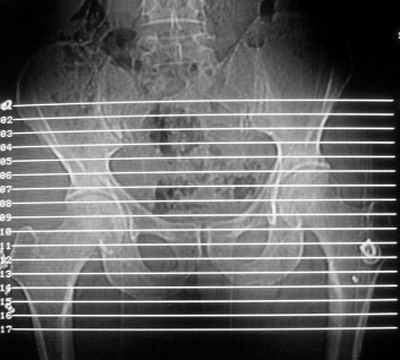

标题: CT16837:M63Y,右臀部巨大软组织包块

患者,男,63岁,自诉3个月前发现右臀部包块,触及疼痛,治疗后缩小。前天突然增大。无高热病史。

给个骨窗,判断一下肿块是否与髂骨有关,肿块内出血是肯定的,至于是感染形成的脓肿还是起源于肌肉或纤维组织的肉瘤则难以确定,不过从影像上看,包膜完整,且环形增厚,病灶下部见斑片状底密度坏死,个人倾向感染可能性大